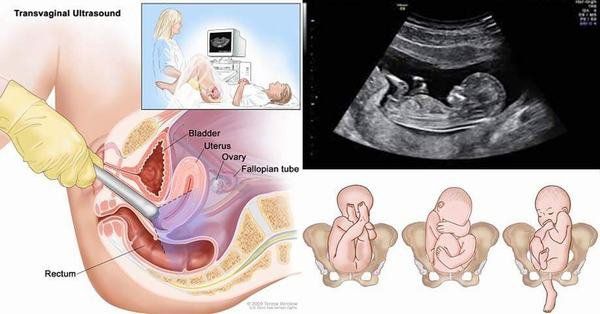

2.Siêu âm thai 6 tuần bằng phương pháp nào?

Bình thường, thai 6 tuần tuổi đã nằm trong tử cung, do đó, thông qua hình ảnh siêu âm thì mẹ đã có thể nhìn thấy những hình ảnh đầu tiên của phôi thai. Hiện nay, siêu âm thai 6 tuần tuổi có thể thực hiện theo 2 phương pháp khác nhau, đem lại kết quả khá chính xác:

2.1. Siêu âm thai 6 tuần tuổi qua ổ bụng

Siêu âm thai qua ổ bụng giúp mẹ nhìn thấy hình ảnh thai nhi sơ khai trong buồng tử cung. Nhược điểm của phương pháp này là hình ảnh của thai nhi đôi lúc sẽ không thấy rõ ràng do sóng siêu âm phải đi qua nhiều lớp mô khác nhau như lớp mỡ, lớp cơ thành bụng...

Để khắc phục nhược điểm này thì cơ sở y tế cần trang bị máy siêu âm hiện đại có độ phân giải cao và chuẩn bị bệnh nhân cần nhịn tiểu để bàng quang căng to. Siêu âm thai 6 tuần tuổi qua ổ bụng

2.2. Siêu âm thai 6 tuần tuổi với đầu dò âm đạo

So với siêu âm thai 6 tuần qua ổ bụng thì siêu âm qua đường âm đạo có ưu điểm vượt trội hơn về độ chính xác cao và hình ảnh rõ nét hơn.

Một loại đầu dò đặc biệt được đưa vào âm đạo của mẹ, đầu dò phát sóng siêu âm truyền vào buồng tử cung của mẹ để ghi nhận các đặc điểm như vị trí, kích thước, mức độ phát triển của thai nhi. Sau đó tái tạo hình ảnh để hiển thị trên màn hình siêu âm, bác sĩ sẽ ghi nhận những bất thường nếu có.